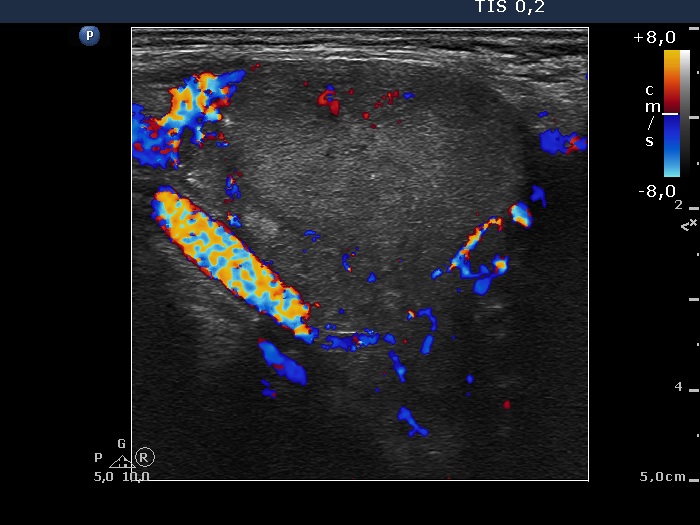

100 consecutive patients with thyroid nodule - Case 36. (ultrasonographic picture 7)

Left lobe, horizontal scan, color Doppler mode. The lesion presents a perindoular blood flow.